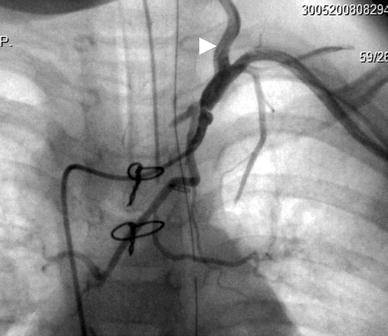

Follow-up selective angiogram of the left subclavian artery showing antegrade flow into the left vertebral artery (arrowhead) after end-to-side anastomosis of the isolated left subclavian artery to the left common carotid artery